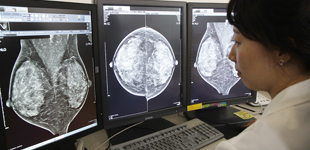

[제주건강보고서 메디컬센터](47)유방영상의학

확진과 수술전 치료계획 수립·추적검사 등 망라유방촬영술·초음파·유선조영술 등젊은여성은 초음파검사 우선 실시의심병소 있을 때는 조직검사 필요 유방암은 미국과 유럽 등 선진국에서는 여성암 중 가장 흔한 암이다. 40…

[제주건강보고서 메디컬센터](45)유방암 바로 알기

젊은 환자들 "이 나이에 무슨 암이…" 후회 막심뚜렷한 자가증상 없고 검진서 발견돼멍울 만져지면 어느정도 진행된 단계정기적 검사 통해 유방건강 체크 중요 K(34·여)씨는 약 1년 전부터 유방에 혹 같은 것이 만져져 병원을 찾…